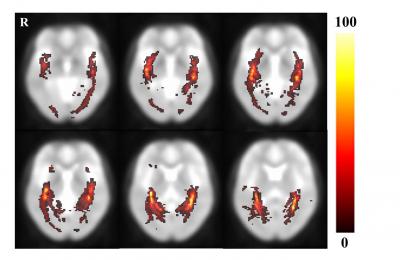

The optic radiation is a dense fiber tract that emerges from the lateral geniculate nucleus and continues to the occipital visual cortex. Especially, the optic radiation is an important fiber structure that conveys visual information from the lateral geniculate nucleus to the primary visual cortex in the occipital lobe. Current studies have focused on the anatomical characteristics of optic radiation fiber tracts in individual brains and on comparisons of the anatomical characteristics of the optic radiation fiber tracts between patient and control groups. Therefore, no diffusion tensor tractography studies of the volumetric information of optic radiation have been conducted without individual brain structure variation. To attain the volumetric information of the optic radiation in normal human brains, Dr. Cheol-Pyo Hong and coworkers from Korea Research Institute of Standards and Science (KRISS) performed diffusion tensor imaging examination in 13 healthy volunteers. Their results showed that the measured optic radiation fiber tract volume was a range of about 0.16% and that the fractional anisotropy value was about 0.53. Moreover, the optic radiation probability fiber pathway that was determined with diffusion tensor tractography-based group mapping was able to detect the location relatively accurately. The methods and results from Dr. Cheol-Pyo Hong and coworkers are helpful in the study of optic radiation fiber tract information, which has been reported in the Neural Regeneration Research (Vol. 9, No. 3, 2014).